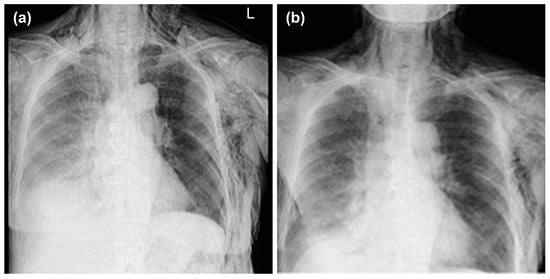

Thoracentesis and abdominocentesis were performed for detailed examination, and 1000 mL of each specimen was obtained. The cell block results of the obtained specimens indicated a suspected metastasis of high-grade serous carcinoma arising from the ovary. A biopsy under general anesthesia was scheduled to confirm ovarian cancer and to select drug therapy. However, after draining 1000 mL of pleural fluid, a large amount of left pleural fluid was still reaccumulated at the second examination two weeks later. Therefore, intubation under general anesthesia was judged to be high-risk. Therefore, the anesthesiologist requested the insertion of a left thoracic drain the day before. After the insertion of a thoracic drain, the patient was found to be COVID-19-positive on preoperative screening, and as a result, the patient’s biopsy surgery was postponed and the left thoracic drain was planned to be removed. However, considering that removing the drain immediately following insertion would be detrimental to the patient, removal was scheduled for the next day, to be followed by observation of the patient for several additional days. As planned, the drain was removed the day after insertion. However, approximately one hour following the drain’s removal, mediastinal and subcutaneous emphysema suddenly developed, with the patient also complaining of mild dyspnea. A left pneumothorax was then diagnosed using chest radiography. In addition, chest radiographic findings included mediastinal and subcutaneous emphysema observed in the anterior mediastinum and on the left side of the chest. Subsequently, a drain (20 Fr) was placed in the patient’s left thoracic cavity immediately after confirming the X-ray (Figure 2).

Figure 2.

Mediastinal and subcutaneous emphysema was observed in the anterior mediastinum and on the left sides of the chest, respectively.